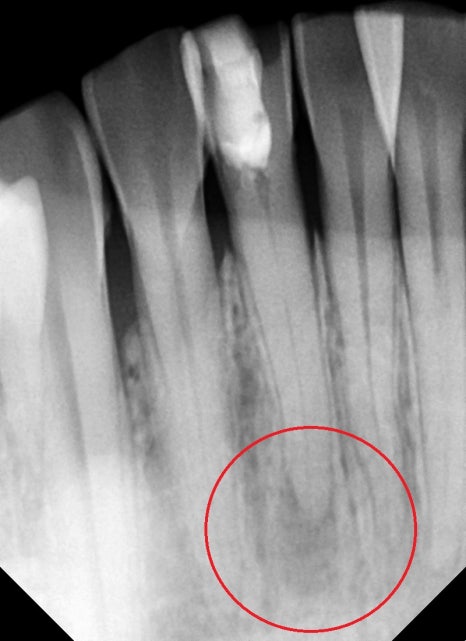

엑스레이 사진상에서 아래 앞니 뿌리 끝이 염증이 생긴 것을 확인할 수 있었습니다.

신경치료가 중단된 상태로 보이고, 치아 주변의 수복물은 오래되어 누출이 일어났을 것이고

뿌리끝 쪽 신경관이 석회화되어있어서 길을 조금씩 넓혀들어가는데 집중을 했습니다.

뿌리 쪽 염증으로 인해 주변 골이 녹아있는 상태에서 뿌리 외부와 내부를

차단하기 위해 뿌리 주변을 약재가 막게끔 충분히 밀봉을 했습니다.